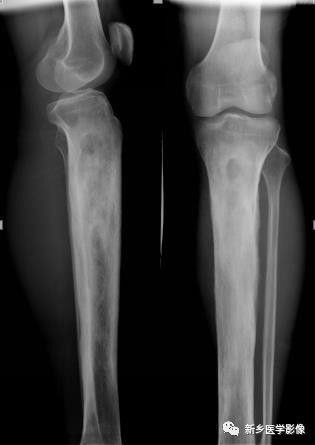

骨质硬化X线图像

小腿上段正侧位X线片示胫骨上段骨质密度增高,骨质增生硬化,其内见骨质破坏区。